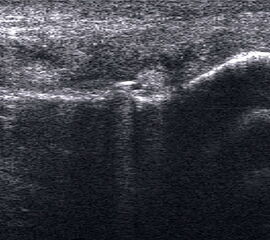

Echogene Verdickung im Subkutangewebe bei Lymphödem

Abbildung 8

Lagerung: Rückenlage.

Schnittebene: Ventraler LS über dem OSG.

Referenzstrukturen: Distale Tibia und Talusrolle, darüber Gelenkkapsel. Befunde: Echogene Verdickung subkutan (Abb. 8), hier peronäal oberhalb des OSG. Bei Varicosis sind in der Subkutis erweiterte Venenkomplexe mit echoarmem Lumen und positivem Doppler-Signal zu sehen.